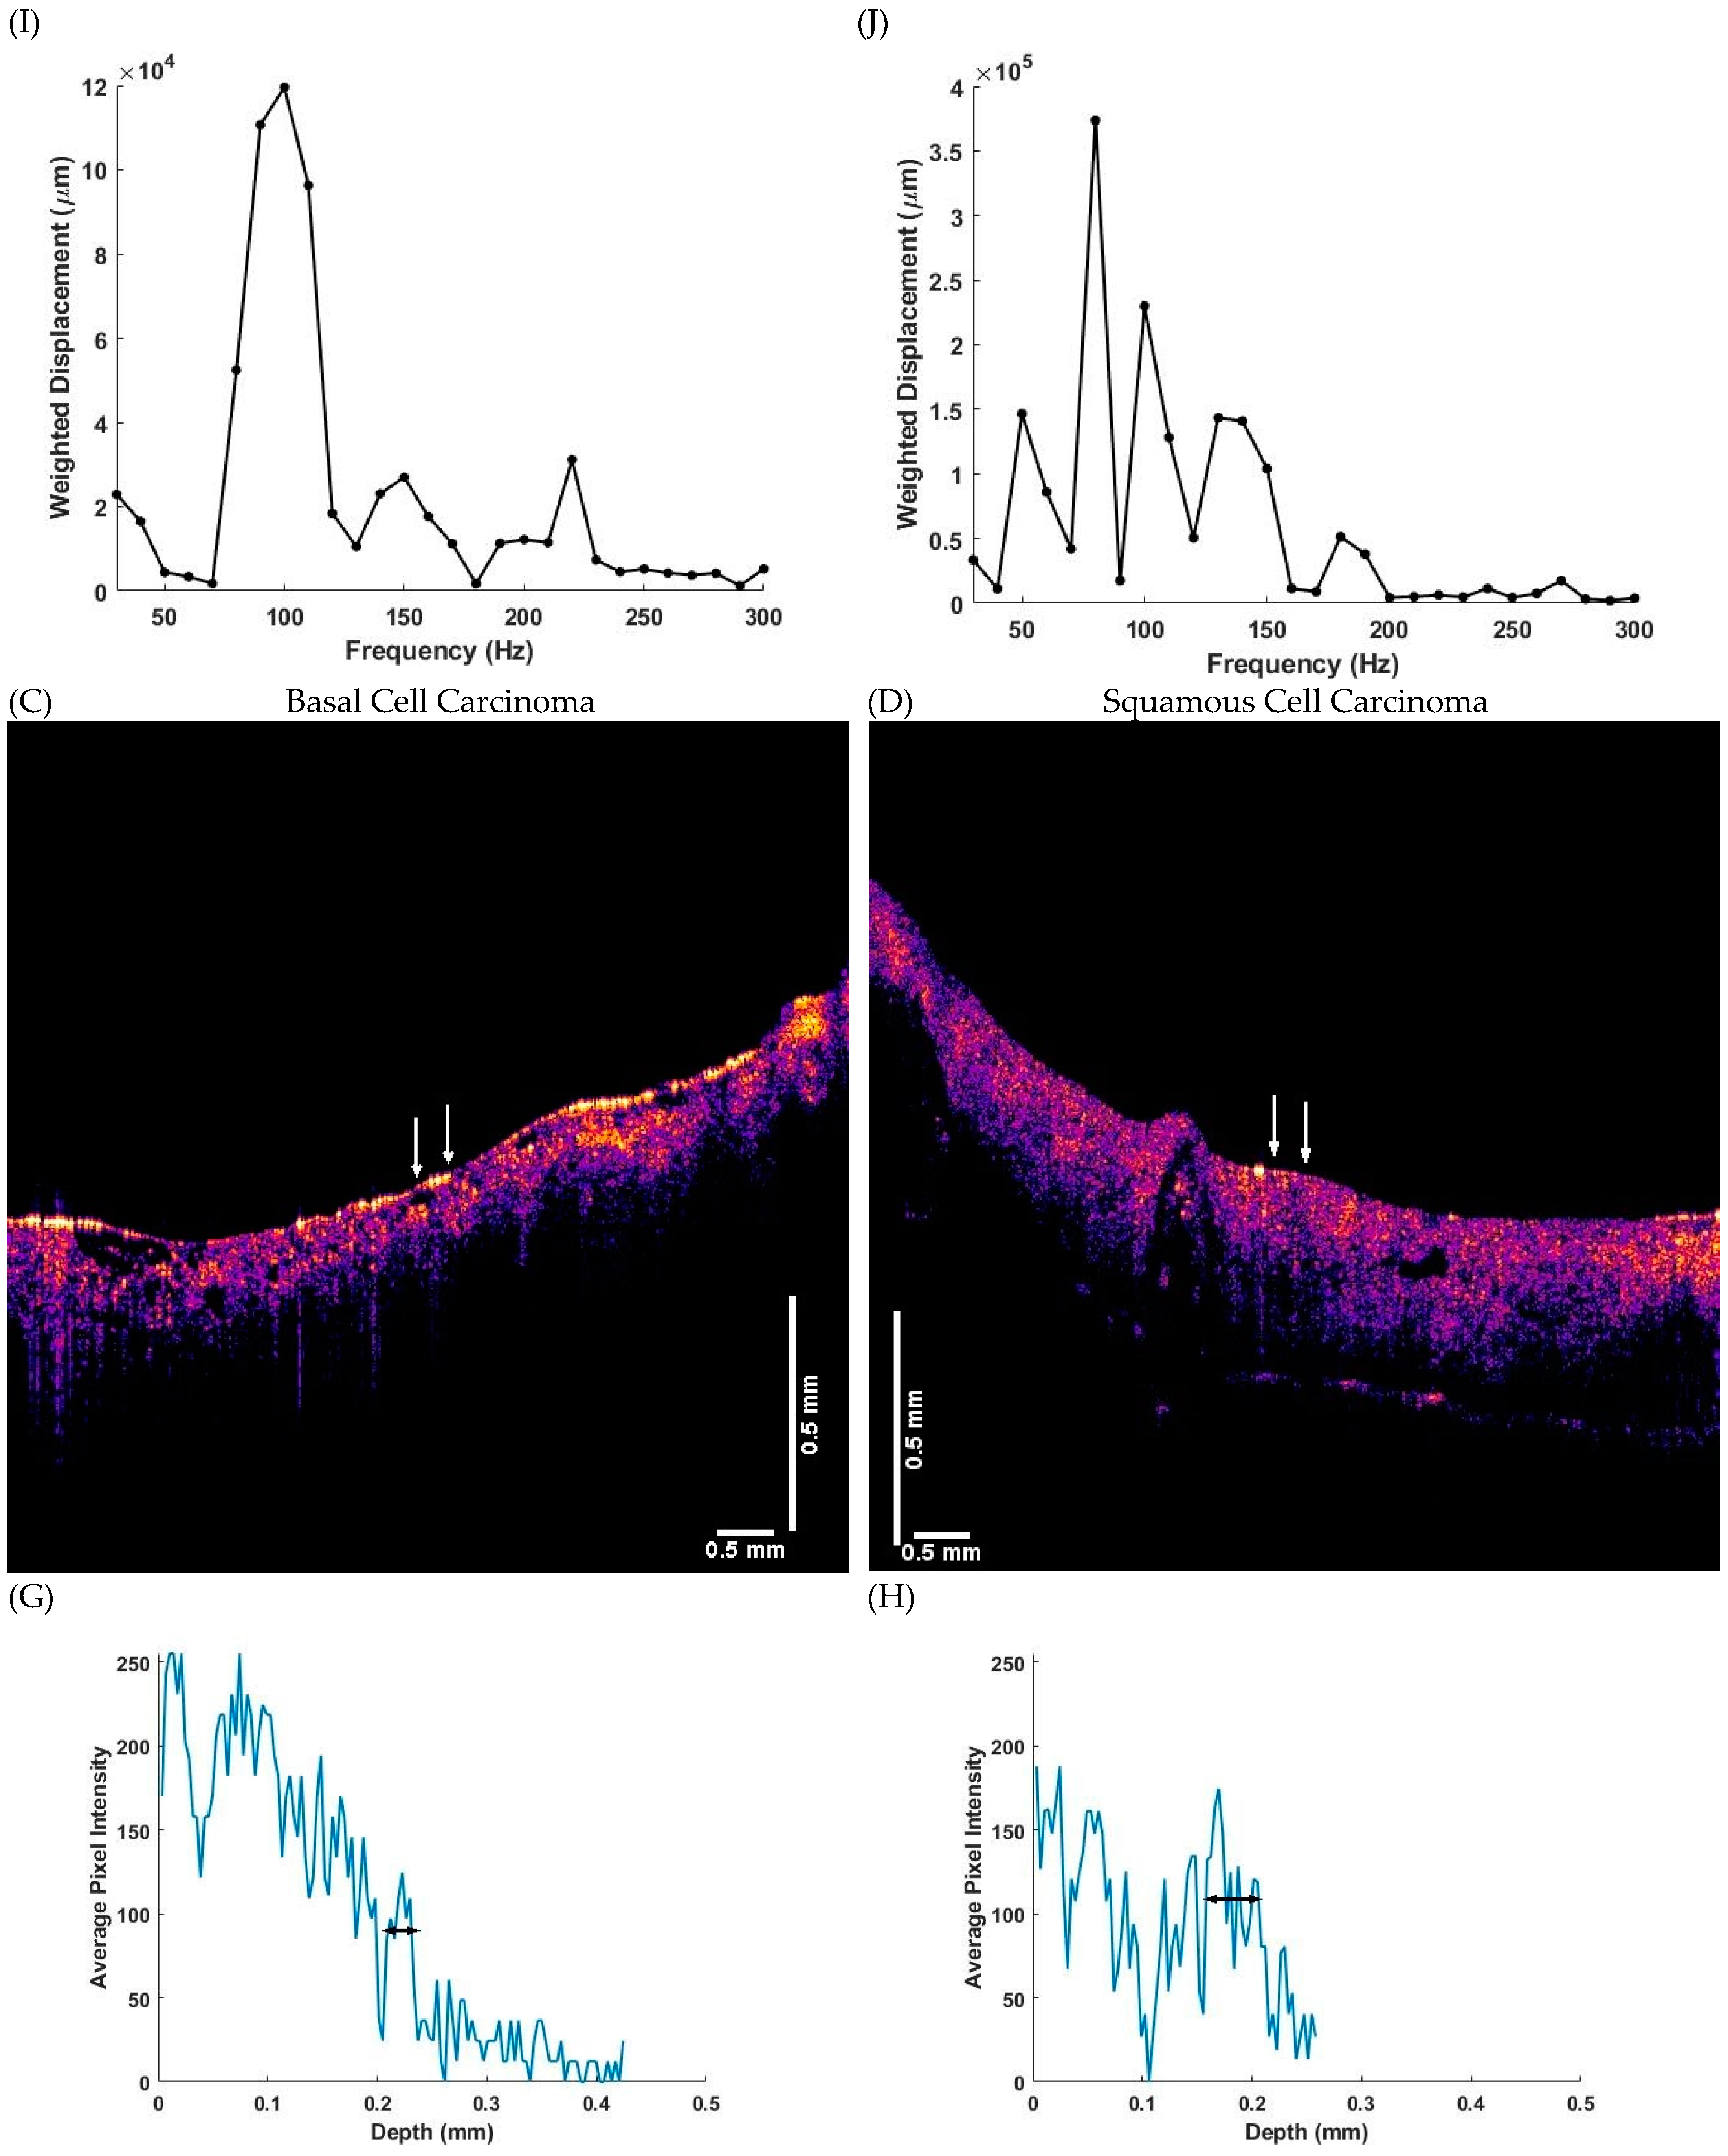

2.2. OCT Images and Scans of Pixel Intensity Versus Depth Measurements

2.3. Measurement of Resonant Frequency and the Elastic Modulus

3. Results

4. Discussion

4.1. The 80 Hz Peak

4.2. The 130 Hz Peak

4.3. The 260 Hz Peak